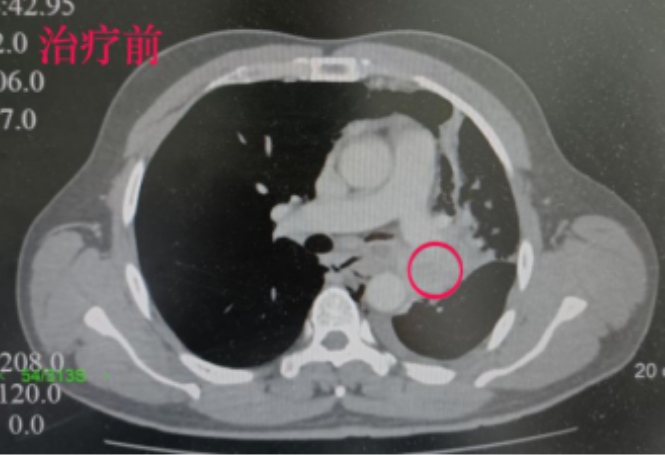

复查CT结果显示,李叔肺部的肿瘤已从5.0cm*4.4cm*4.6cm缩小到2.0*1.1*1.0cm,体积奇迹般缩小了90%以上!肺门纵膈淋巴结也明显缩小。复查PET/CT检查提示原为阳性的对侧肺门淋巴结,在治疗后转阴。